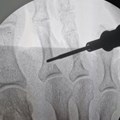

Surgical ProceduresIn a first for South Africa, a robotic procedure successfully removes kidney for donation28 Aug 2025

Medical AidGap cover gives you the gift of choice when it comes to robotic assisted surgeryTony Singleton 11 Nov 2022